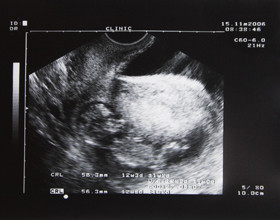

Trois échographies en 9 mois de grossesse : pour les parents (les papas sont les bienvenus), de tendres rendez-vous avec le bébé.

Le médecin va promener une sonde sur le ventre. Celle-ci émet des ultrasons qui permettent de visualiser le bébé sur un écran.

Vous aurez trois échographies au cours de votre grossesse afin de contrôler l’évolution du bébé et de diagnostiquer des anomalies éventuelles. Toutefois, cette technique n’est pas fiable à 100%. Le médecin ne peut pas absolument tout détecter lors d’une échographie.